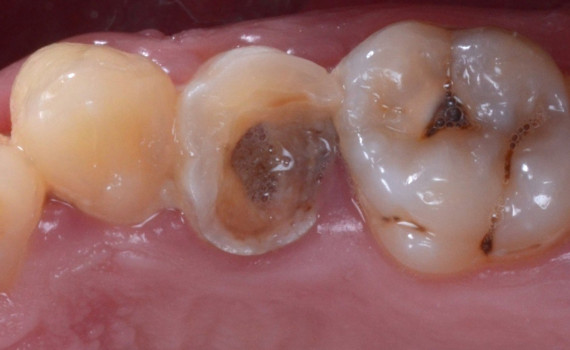

Mihaela a ajuns la noi cu plombe foarte vechi, uzate și cu discolorații, dar și cu o fațetă pe unul din dinții frontali, care nu arăta deloc bine. Colegii stomatologi i-au refăcut plombele vechi și fațeta.

Protejarea molarului cu incrustatie onlay.